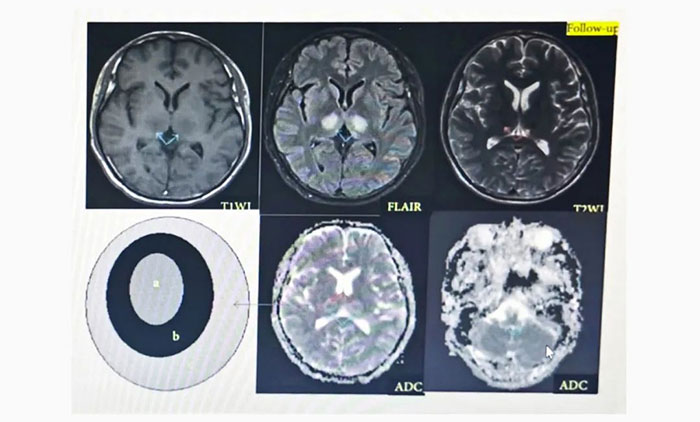

▲ ANE影像学:具有多灶性、对称性脑损害的特点,病变内出血和环形强化为经典影像学表现。ADC加权像上呈特征性“同心圆结构”。

入院查体,体温36.5℃,神志模糊,言语含糊,理解判断及自知力下降,定向力、计算力、记忆力检查不合作;四肢肌力检查不合作,共济运动不能完成。MMSE及MoCA量表评分不能配合。头颅MRI:双侧额顶叶脑白质脱髓鞘改变。并且新冠病毒抗体IgG阳性。

入院后结合患者病史:快速进展认知障碍、行动迟缓、二便障碍,头颅影像双侧脑室旁对称大片白质脱髓鞘病变,并且患者既往体健,无其他基础疾病,排除代谢、中毒、缺氧等因素,结合患者发病特点,经会诊后考虑为自身免疫性脑病、新冠病毒相关的急性坏死性脑病。

▲ 患者影像变化